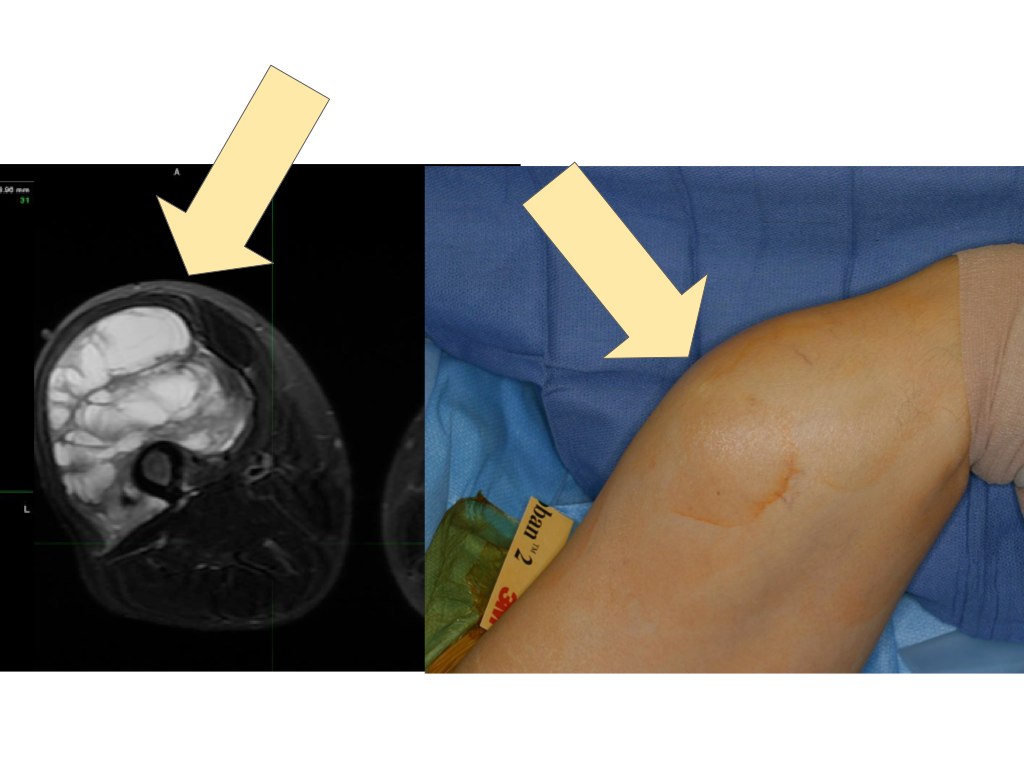

Same patient one year later, following distal femur resection & endoprosthetic reconstruction

Removal of soft tissue sarcomas is among the most common surgeries performed by orthopedic oncologists. The size and location of the tumor will generally determine how much function the patient will lose after surgery. If the tumor is located in the inside or the back of the thigh - common locations for soft tissue sarcomas - patients can expect to lose only limited amount of function, even with large resections.

However, these surgeries can be very complex and attention to detail is very important. Typically MRI is performed before and after radiation and extensive counseling of the patient is done before surgery. After surgery, physical and occupational therapy and sometimes lymphedema therapy (for swelling) are needed for a period of time. Careful planning and an experienced team are important in ensuring the best possible outcome.